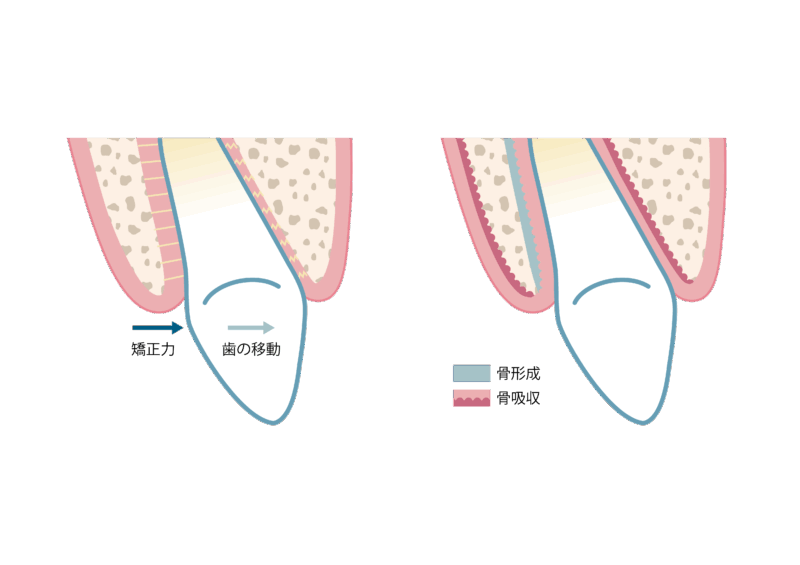

矯正治療の痛みは、歯が“動いている証拠”でもあります。

矯正装置によって歯に力が加わると、歯の周りの「歯根膜」というクッションのような組織が反応し、少しずつ骨が作り変えられます。このとき、周囲の組織に炎症が起きるため、ズーンとしたり、押されるような痛みが生じます。

炎症と聞くと不安に感じるかもしれませんが、これは正常な反応であり、適切にコントロールされた力を加えているため心配はいりません。